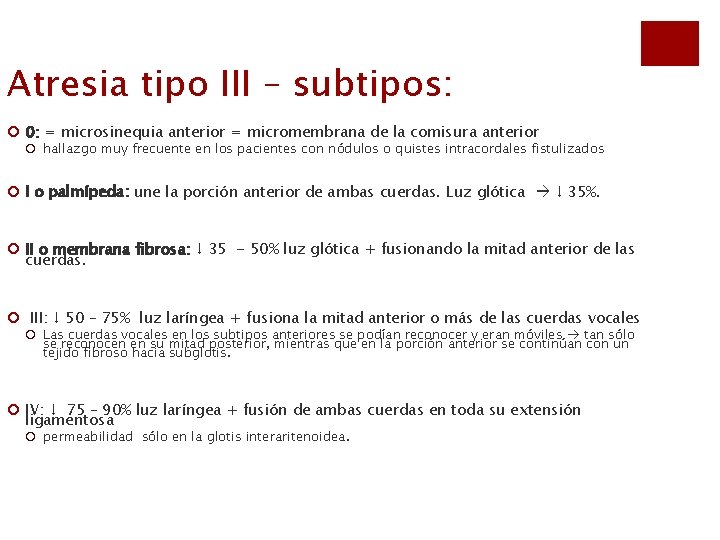

Atresia tipo III – subtipos: ¡ 0: = microsinequia anterior = micromembrana de la comisura anterior ¡ hallazgo muy frecuente en los pacientes con nódulos o quistes intracordales fistulizados ¡ I o palmípeda: une la porción anterior de ambas cuerdas. Luz glótica ↓ 35%. ¡ II o membrana fibrosa: ↓ 35 - 50% luz glótica + fusionando la mitad anterior de las cuerdas. ¡ III: ↓ 50 – 75% luz laríngea + fusiona la mitad anterior o más de las cuerdas vocales ¡ Las cuerdas vocales en los subtipos anteriores se podían reconocer y eran móviles tan sólo se reconocen en su mitad posterior, mientras que en la porción anterior se continúan con un tejido fibroso hacia subglotis. ¡ IV: ↓ 75 – 90% luz laríngea + fusión de ambas cuerdas en toda su extensión ligamentosa ¡ permeabilidad sólo en la glotis interaritenoidea.